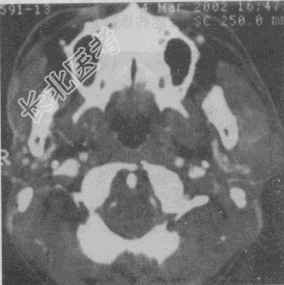

- 单项选择题女性,45岁。发现左侧腮部肿块1年余, 逐渐长大,无明显不适。CT检查如图所示, 应首先考虑

A、腮腺囊腺淋巴瘤

B、血管瘤

C、脂肪瘤

D、淋巴瘤

E、多形性腺瘤